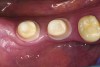

Fig 4. Stereolithography resin model with IPS e.max (Ivoclar Vivadent) crowns.

Figure 4

Fig 5. Zirconia custom abutments delivered.

Figure 5

Fig 6. All-ceramic (IPS e.max) crowns delivered with incisal composite restorations on the central incisors.

Figure 6

An example of the process using the True Definition Scanner to digitally record the position of a Biomet3i (Biomet, Inc., www.biomet.com) implant using an Encode® (Biomet) abutment can be seen in Figure 1 through Figure 6. The Encode healing abutment is placed on the implant to extend at least 1 mm supragingivally to make its geometry available for intraoral scanning (Figure 1). The True Definition Scanner records the intraoral data (Figure 2), and the digital file is transmitted electronically to the Biomet 3i Design Lab for design (Figure 3) and fabrication of the desired custom abutment. Once the design file is approved by the laboratory, the abutment is inserted into the digital file, and an SLA model (Figure 4) can be processed for fabrication of the final restoration (Figure 5 and Figure 6).